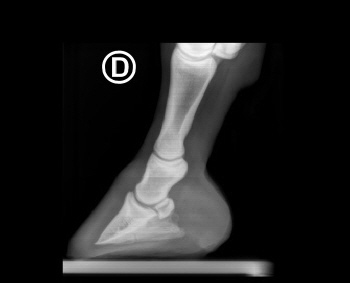

Röntgenbilder akuter- und chronischer Hufrehehufe vorher und nachher

Nachstehend stellen wir einige Röntgenbilder von Hufrehepferden ins Netz, welche das Vorher und das Nachher zeigen. Wir möchten damit aufzeigen, dass durch eine richtige Hufbearbeitung ein Hufbein wieder in eine korrekte Lage innerhalb der Hornkapsel zu liegen kommen kann.

In besonders schweren Fällen wurde doch zumindest eine Optimierung angestrebt.

vorher